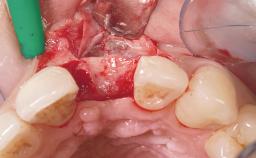

A 36-year-old female patient was referred for the replacement of the upper left central incisor (tooth 21), which had fractured. Although the tooth had been asymptomatic for many years, the crown began to loosen, at which time she presented to her dentist for an assessment. Teeth 21 and 22 had both been endodontically treated many years previously. She was a healthy individual and a non-smoker.

The crown of tooth 21 was splinted to the adjacent teeth with composite resin, and the gingiva was inflamed.

| Bone Augmentation | Horizontal|Staged |

| Soft Tissue Grafting | Simultaneous |